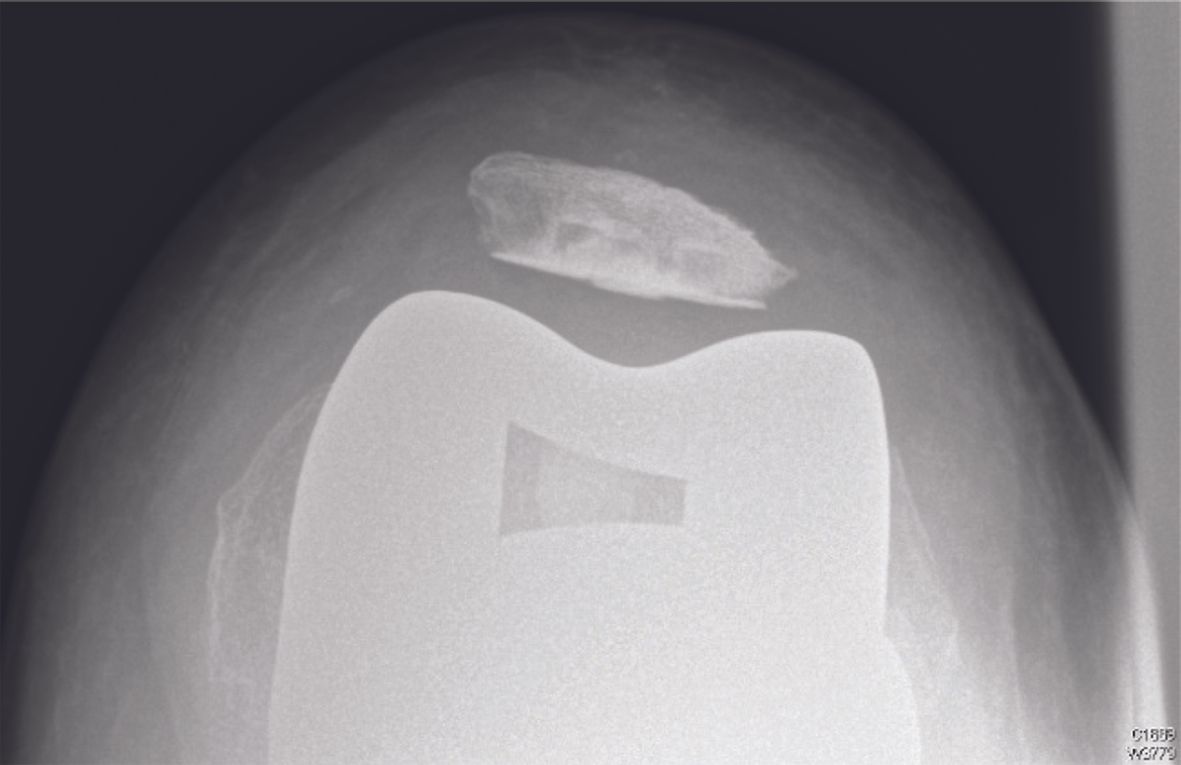

1. Objective patellar instability with patellar dislocation

These patients have total or partial lateral dislocation of the patella (Fig. 1). The cause is rotational malalignment of the femur and/or tibia implant (Fig. 2) or severe torsional limb malalignment with increased femur anteversion or excessive tibia internal rotation or both.